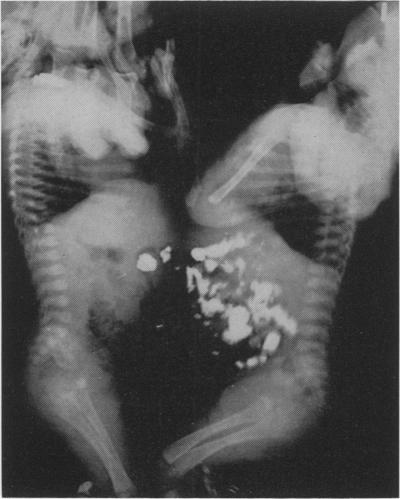

WILSON H, STORER E H

Ann Surg. 1957 May;145(5):718-25. doi: 10.1097/00000658-195705000-00014.